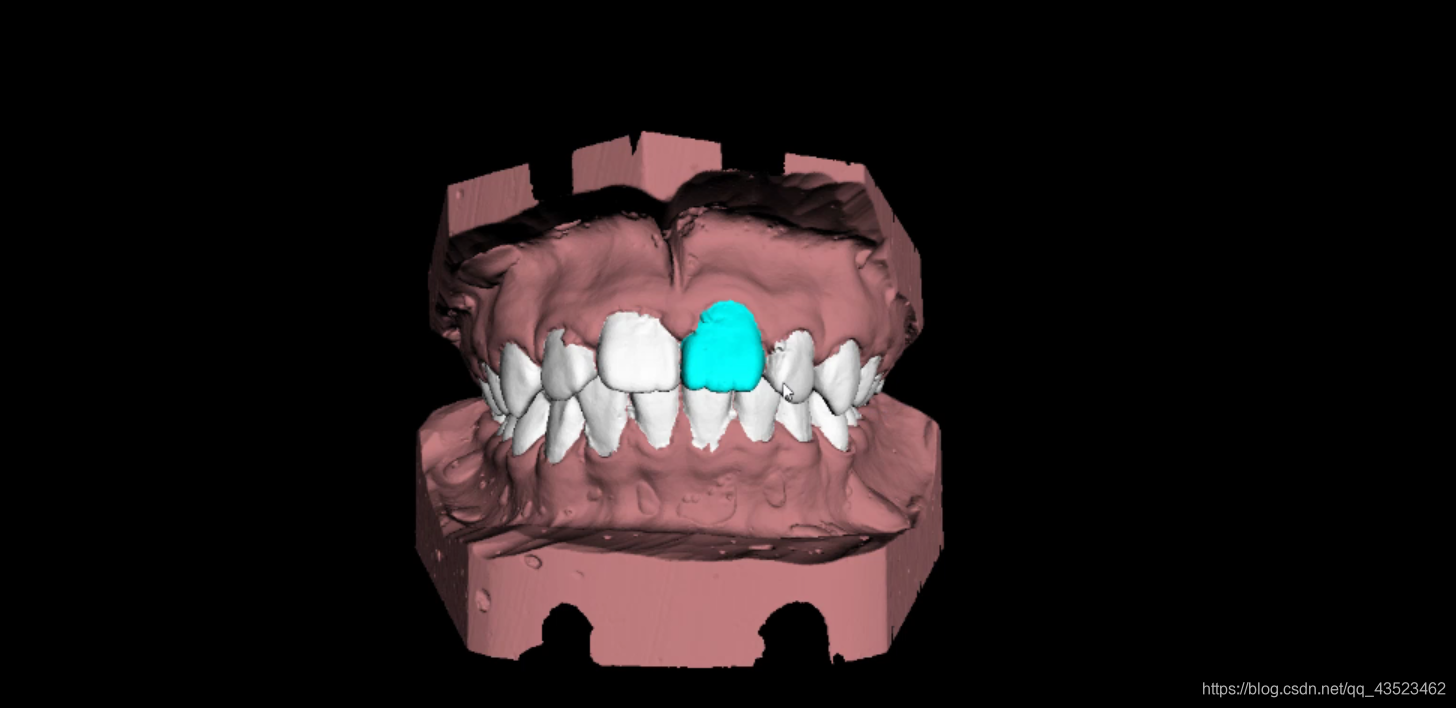

由于需要对口扫模型的分类结果进行展示,一个比较好的展示形式是选择不同的分类,就对分类出来的那个部位进行高亮或者单独显示。

对一个完整的模型进行某一部分的高亮的和单独显示比较困难,这也是工作迟迟未完成的原因之一。为此采取折中方案,使用python程序将完整的整个模型进行划分,生成多个不同部位的模型子文件,再在前端选择显示不同的子文件,这样能够方便快速的完成模型部位的高亮和单独显示。

部位高亮效果:

可以看到效果不错,工作完成的还可以。